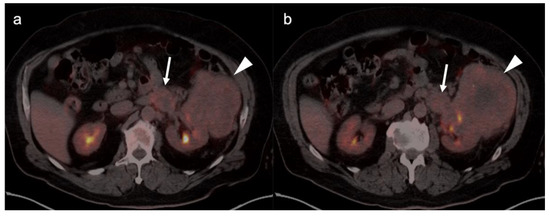

- Park, J.W.; Jo, M.K.; Lee, H.M. Significance of18F-fluorodeoxyglucose positron-emission tomography/computed tomography for the postoperative surveillance of advanced renal cell carcinoma. Br. J. Urol. 2009, 103, 615–619. [Google Scholar] [CrossRef]

- Alongi, P.; Picchio, M.; Zattoni, F.; Spallino, M.; Gianolli, L.; Saladini, G.; Evangelista, L. Recurrent renal cell carcinoma: Clinical and prognostic value of FDG PET/CT. Eur. J. Pediatr. 2015, 43, 464–473. [Google Scholar] [CrossRef] [PubMed]

- Karivedu, V.; Jain, A.L.; Eluvathingal, T.J.; Sidana, A. Role of Positron Emission Tomography Imaging in Metabolically Active Renal Cell Carcinoma. Curr. Urol. Rep. 2019, 20, 56. [Google Scholar] [CrossRef] [PubMed]

- Fuser, D.; Hedberg, M.L.; Dehner, L.P.; Dehdashti, F.; Siegel, B.A. Extensive Metastatic Sarcomatoid Renal Cell Carcinoma Evaluated by 18F-FDG PET/CT: A Case Report and Review of Literature. J. Kidney Cancer VHL 2018, 5, 1–6. [Google Scholar] [CrossRef] [PubMed]